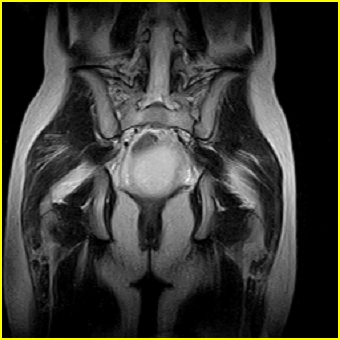

女、15岁、下腹疼痛2天,排尿困难1天。查体:处女膜闭锁,距处女膜约4至5cm处扪及一约5cm直径的圆形包块,张力较高,触痛明显、欠活动。b超提示子宫增大伴宫内增强回声团。

影像意见:子宫直肠陷凹积血。

更正影像意见:阴道积血。

处女膜闭锁,阴道积血

处女膜闭锁,阴道积血,子宫积血.

先天性处女膜闭锁,伴阴道积血,不除外先天性阴道粘液囊肿形成。

阴道积血,子宫积血.

子宫及阴道积血。

处女膜闭锁,伴子宫及阴道积血.